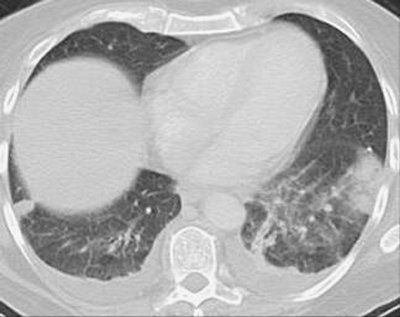

FIGURE 17-24. Bilateral pulmonary infarcts. CT shows bilateral pleural-based opacities characteristic of pulmonary infarcts.

FIGURE 17-25. Old pulmonary infarcts. CT shows bilateral subpleural linear opacities, representing scarring from previous pulmonary infarcts.

Pulmonary infarction results in airspace opacities that are usually multifocal and predominantly in the lower lungs. They usually appear within 12 to 24 hours after the embolic event. The opacities are classically peripheral, with a triangular or rounded shape (thus the term Hampton hump), and they are always in contact with the pleural surfaces (Figs. 17-23 and 17-24). The apex of the opacity is directed toward the lung hilum. Occasionally, lobar opacity resembling pneumonia can occur. Air bronchograms are rarely present. It is important to note that the opacities can represent a combination of pulmonary hemorrhage and atelectasis without infarction, in which case clearing occurs within a week. Infarction takes several months to resolve, often with residual scarring (Fig. 17-25). As infarcts resolve, they melt away "like an ice cube" (giving rise

P.283

to the so-called "melting ice cube sign"; Fig. 2-16). The opacity clears from the periphery first, whereas in pneumonia the opacity clears homogeneously, both centrally and peripherally at the same time. Cavitation can occur within infarcts but is rare without coexisting infection, either secondary infection of an infarct or a result of septic emboli or vasculitis.